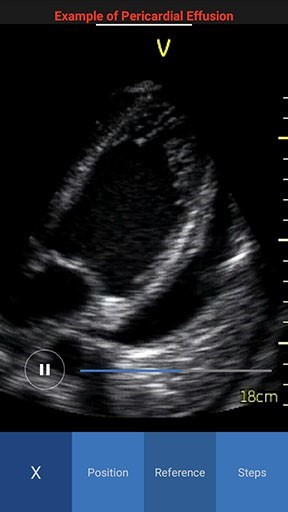

Scan Coach reference window displays with three tabs - Reference, Position and Steps.

- Reference - Provides access to multiple ultrasound image examples for normal view and a few common pathologies for the current scan plane. You can access all available reference images swiping left or right.

NOTE: By default the reference image tab is activated when you press the info icon for the first time. The white color in the image header represents an example of a normal image, while red color represents an example of a pathology image.

Reference image Pathology